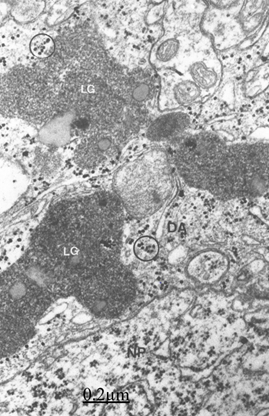

Electron microscopy images of astrocytes at low magnification show nerve cells charged of numerous lipofucsin granules (Figure 11). Besides, we report edematous and ischemic oligodendrocytes (Figure 12).25,26

Figure 11 Brain traumas, subdural hematoma. Non-pryramidal nerve cell (NP) surrounded by a satellite and peripheral dense astrocyte (DA) containing large lipofucsin granules (LG) and glycogen granules (circles).